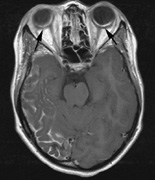

Intracranial leptomeningeal capillary vascular malformation (Figs. 21 and 22) is associated with seizures and contralateral neuromuscular weakness. Central nervous system involvement correlates highly with ipsilateral involvement of the V1 dermatome by a PWS.208,218

Fig. 22. Axial T2-weighted (a) and coronal T1-weighted (b) images of a 16-year-old boy with a port-wine lesion over the right side of his face. The right hemisphere is markedly atrophic and abnormal draining veins are seen within the right lateral ventricle (arrowheads). (c, d) The entire right hemisphere is covered by an enhancing pial angioma and the choroid plexi are enlarged. Enhancing retinal angiomas (arrows), typical of Sturge-Weber syndrome, are seen in (d).